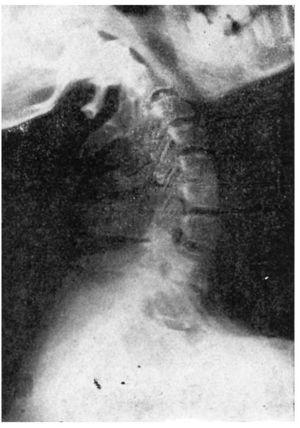

Hay que hacer radiografías de tipo funcional, es decir, de perfil en flexión y en extensión máximas, observando si además de una discosis hay hipermovilidad o inestabilidad en la columna cervical que se estudia.

La lesión es evidente en los discos con disminución evidente de su altura, con reacción ósea que ensancha las caras superior e inferior de las vértebras afectadas; los osteofitos se observan tanto en el borde anterior como en el posterior, algunas veces con evidente protusión hacia el conducto medular. Los discos más habitualmente afectados son el 5.o, 6.o, y el 7.o; también se afecta el 4.o, y 5.o, pero menos. Los discos afectados a veces son dos o tres, y a veces es sólo uno.

El síndrome clínico, lo mismo puede existir por irritación nerviosa o cálculo-nerviosa en el agujero de conjunción, por un osteofito pósterolateral o por una hernia discal media o lateral, así como por una inestabilidad vertebral cuyo exceso de movilidad provoca también un síndrome cervical. Por la tanto, en la observación radiológica tanto valor puede tener la discosis como la inestabilidad de alguna vértebra (fig. 2).

Figura 2.Causas de irritación de los nervios raquídeos.